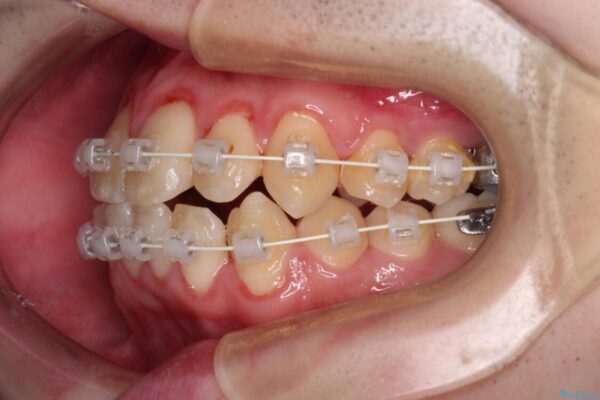

治療途中

• 全顎的なクロスバイト 補助装置を用いてワイヤー矯正 治療途中画像

シザーズバイト改善のために補助装置を使用しながら、ワイヤー装置にて全体の歯列を整えることとしました。

シザーズバイトは強く咬合する奥歯を移動させるため、多くの場合においてワイヤー矯正の装置のみでは改善が困難となります。

奥歯の咬み合わせ改善は治療初期からしっかりとアプローチする必要があるため、補助装置を積極的に利用します。